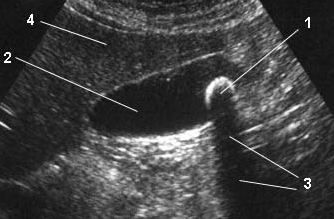

Вот они, драгоценные:

1. камень желчного пузыря 2. полость желчного пузыря 3. акустическая тень камня 4. ткань печени